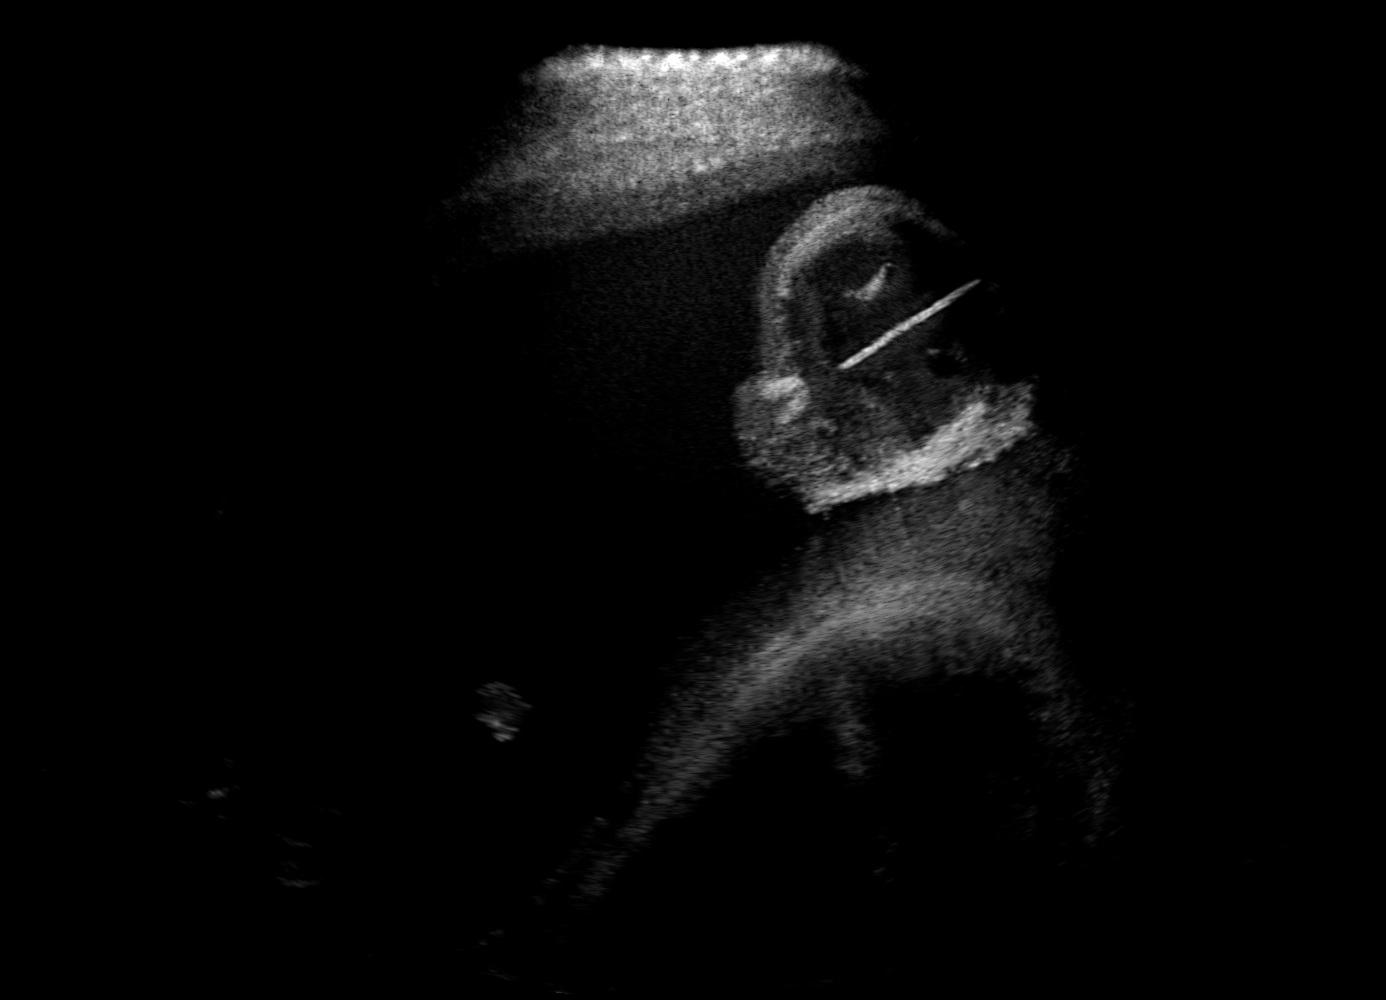

Qualitative evaluation.

Fig. 2 depicts the qualitative results for all the models mentioned above, with arrows pointing at structures relevant to discussion points below. The visual results of the ablated variants of SA2H show substantial quality degradation compared to the full SA2H model, demonstrating the importance of each proposed architectural contribution. Given only segmentation map in the network input, SA2H-att fails to generate acoustic shadows, e.g. those cast by the ribs. Detailed structures such as the cervical vertebrae are blurred out in the SA2H-concat results, which also contain hallucinated structures mainly due to insufficient preservation of input information along the encoding-decoding path. With SA2H-conv, checkerboard artefacts are observed due to the lack of proposed additional stride-1 convolutional layers. SA2H-noise without any explicit noise input is seen to be sub-optimal at generating textural details. The baseline method NSA2H fails to preserve anatomical structures and acoustic shadows in all cases, while the simulated textures also show significant artefacts such as checkerboard patterns. Realism of different simulation aspects may become relevant given different clinical applications and scenarios. For instance, improved structural preservation, e.g. with the hyperechoic bony structures such as the skull and the ribs, of the final model over its ablated variants and NSA2H may prove relevant in fetal head measurements, while the textural improvements facilitating screening fetal organ maturity, e.g. lungs. Compared to the silver-standard model LSA2H with a low-quality rendered image as additional input, SA2H is seen to be on par in structural preservation. Note that shadowing on homogenous regions (e.g. the rib shadowing on the homogenous lung region on the 4th column of Fig. 2) with our proposed method SA2H is represented more faithfully compared to LSA2H, whereas shadows on structurally complex regions (e.g. the skull shadowing around the heart and surrounding tissues on the 3rd column of Fig. 2) are suboptimal with our SA2H. Therefore, one may have to evaluate our method given particular simulation tasks, e.g. its clinical validity for fetal heart exams. However, even with low quality rendered images, LSA2H leads to artificial enhancements of intensities, lack of acoustic shadows, and low-quality textures especially near the probe, for which SA2H yields satisfactory results as illustrated in Fig. 2.

(a) Target

(b) SA2H

(c) SA2H-att

(d) SA2H-concat

(e) SA2H-conv

(f) SA2H-noise

(g) NSA2H

(h) LSA2H